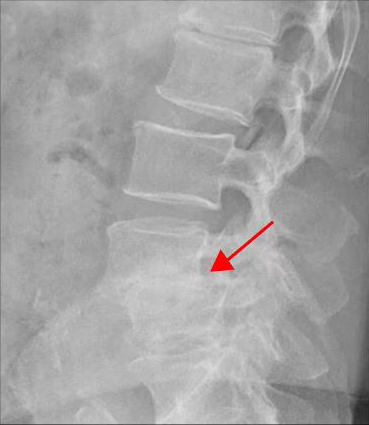

<4-5번 추간공협착증>

<4-5번 척추전방전위증>

이 환자분의 허리 MRI를 보면 4번, 5번 오른쪽에 심한 추간공협착증과 2단계의 척추전방전위증이 있는데, 특히 척추전방전위증 때문에 추간공이 많이 좁아져 있는 상태입니다. 또 왼쪽의 다른 마디에 디스크 파열이 있으나 환자분이 왼쪽으로는 증상이 전혀 없는 것으로 보아 이 디스크 파열은 통증을 일으키지 않는 무증상의 디스크 파열입니다.

이렇듯 4번, 5번 마디의 심한 추간공협착증과 척추전방전위증으로 인해 이 환자분은 다리에 마비가 왔고, 발목에 힘이 빠져 거의 걷지 못하는 상태였습니다. 새벽에 잠에서 깨 화장실을 갈 때는 네 발로 기어갈 정도로 증상이 심했습니다. 신경주사도 많이 맞아봤지만 통증이 전혀 줄지 않아서 결국 수술을 결심하셨는데요. 대학병원을 비롯해 정형외과 및 신경외과 등 아홉 군데 병원에서 진료를 받았지만, 어려운 수술이라고 말하면서 척추유합술, 감압술 등 병원마다 제시하는 수술방법이 다 달라 큰 혼란을 겪으셨습니다. 게다가 수술 후 후유증이나 잔존 증상에 대한 물음에 ‘있을 수도 있고 없을 수도 있다’라는 의사의 말에 수술을 고민하던 중 마지막이라는 생각으로 저희 모커리에 내원하셨습니다.